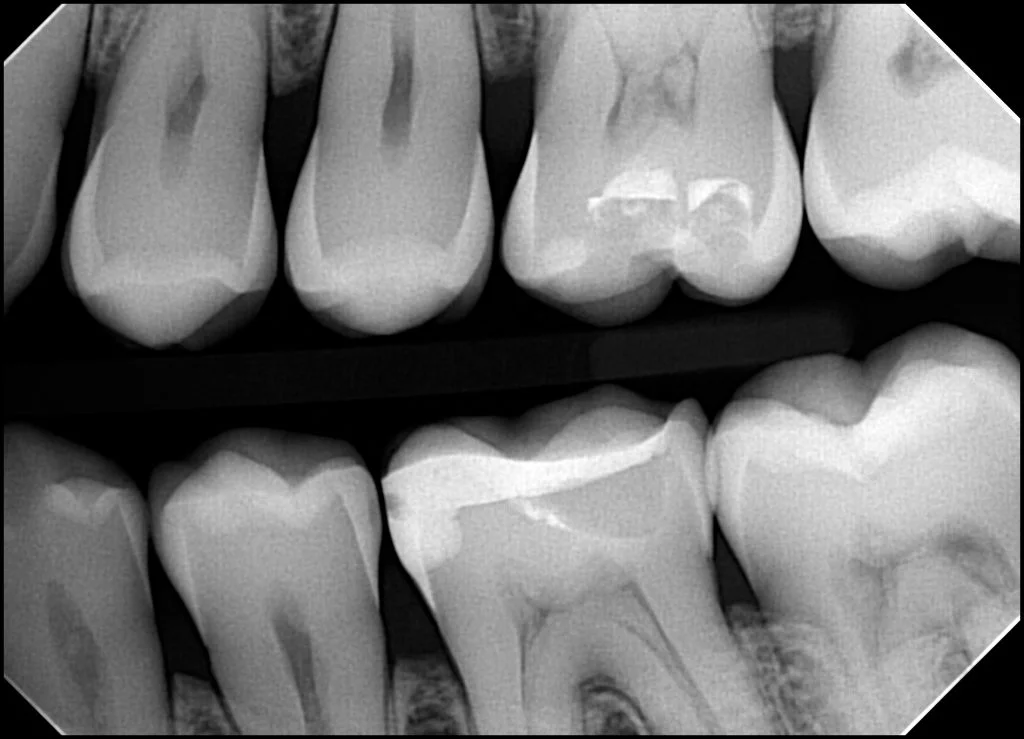

A dental radiograph that is too dark generally means that it was overexposed (i.e. too much radiation hitting the sensor). A dental radiograph that is too light generally means that it was underexposed (i.e. too little radiation hitting the sensor).

It’s also worth noting that some software will auto-adjust the brightness. Sometimes, if the sensor is significantly underexposed for any of the reasons mentioned above, instead of resulting in a light image, it may result in increased graininess. This is due to the software trying to improve the image, when there is less information for the software to work with (due to lack of adequate radiation). It’s a little bit like zooming in on a low resolution image.